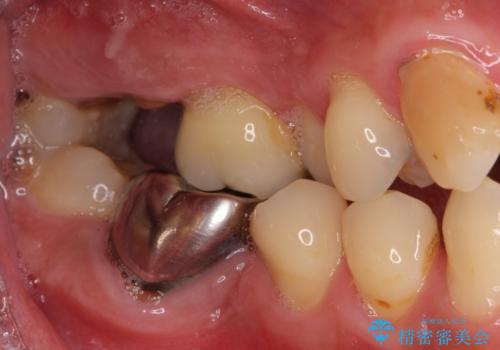

- 前歯や奥歯の虫歯を放置しており、それらの治療を契機に真っ白な歯にしたいとのことで来院された患者様です。

咬み合わせを改善するに当たって、抜歯しなければならない歯や歯列の改善が必要な箇所があったため、矯正治療やインプラント治療から始めていくこととしました。

不自然なくらい真っ白にしたいとのことでしたので、透明感のないフルジルコニアクラウンを用いて補綴することとしました。